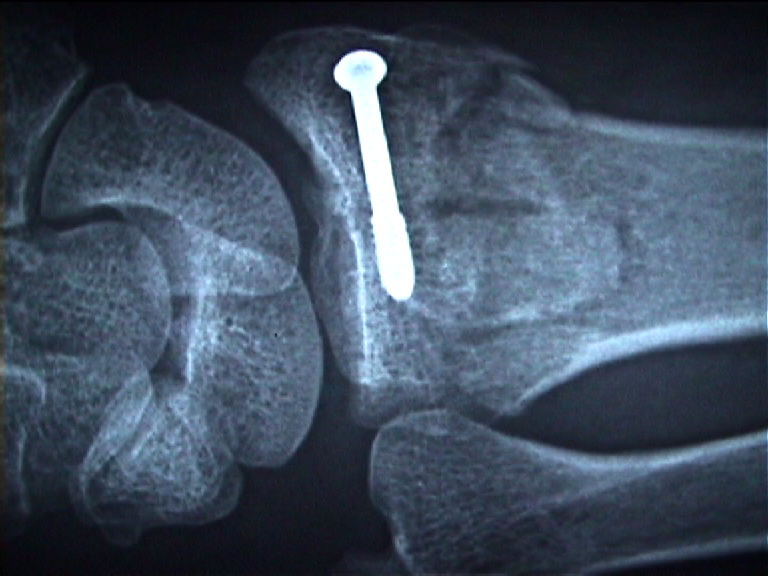

Arztbrief